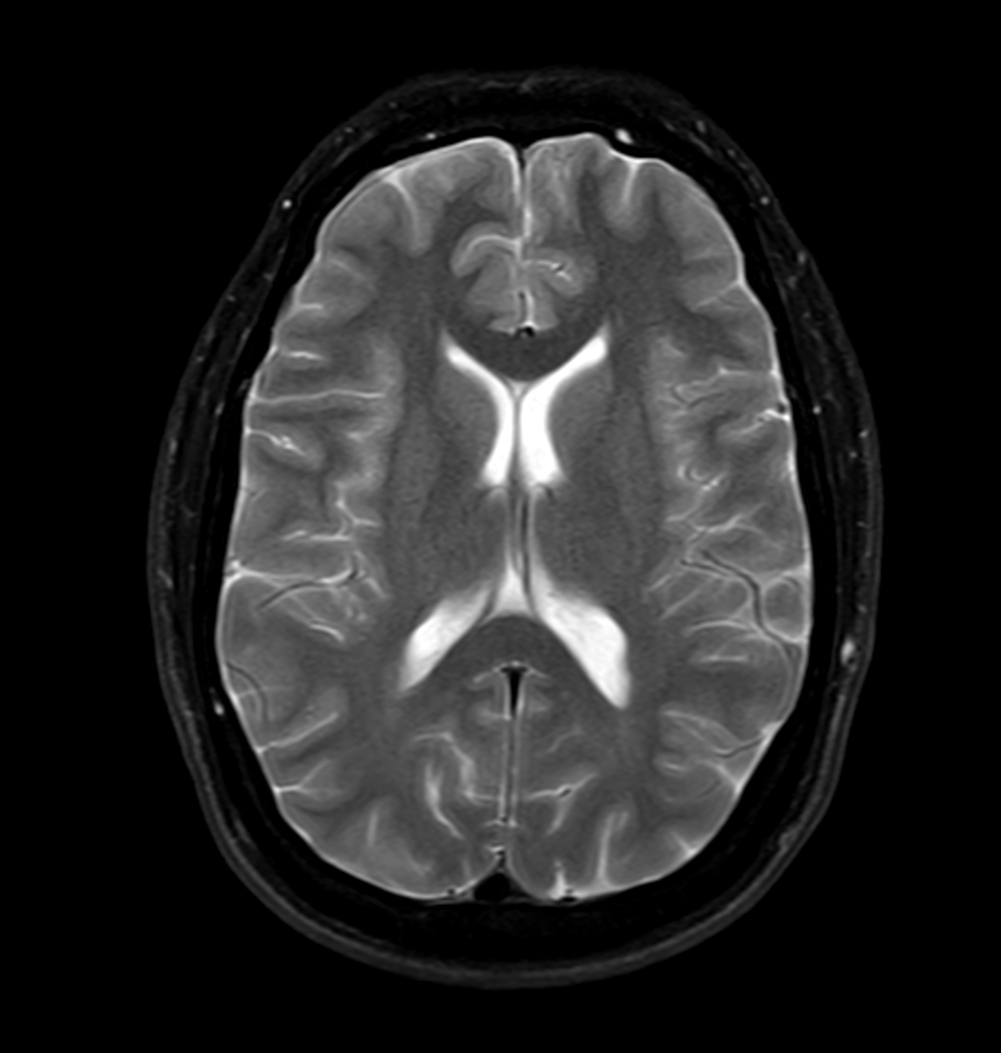

Axial T2w mDIXON XD - T2w TSE (Water only)

Axial T2w mDIXON XD - T2w TSE (In Phase)